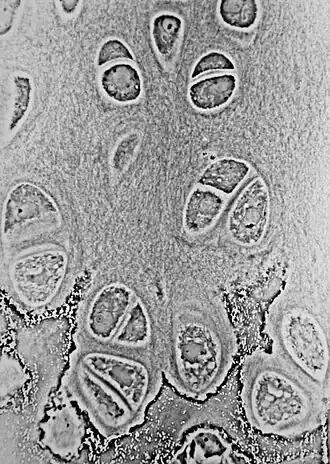

Гиали́новый хрящ (лат. cartilago hyalinis) — разновидность хрящевой ткани; плотный, упругий, стекловидный из-за содержания в нём гомогенного основного вещества, богатого протеогликанами. Гиалиновый хрящ составляет суставные и рёберные хрящи, а также хрящи носа, гортани, эпифиза длинных трубчатых костей, хрящи трахеи и бронхи[1].

Гиалиновым хрящом покрыта суставная поверхность эпифизов. Он обеспечивает подгонку соприкасающихся суставных поверхностей, амортизацию, уменьшает трение сочленяющихся суставных поверхностей. Толщина хряща зависит от функциональной нагрузки на него и в различных суставах колеблется от 1 до 7 мм.

По своим физико-химическим свойствам гиалиновый хрящ представляет собой гель, содержащий 70—80 % воды, 10—15 % органических веществ и 4—7 % минеральных солей. Суставная поверхность хряща гладкая и в условиях нормы увлажнена синовиальной жидкостью. Хрящ не имеет собственной сосудистой сети и нервов и питается, в основном, из суставной жидкости.